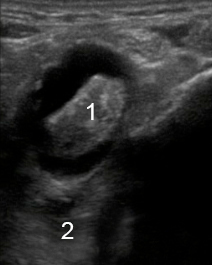

Image - Cheville médiale : Épanchement du long fléchisseur de l'hallux, Coupe transverse

1. Long fléchisseur de l'hallux

2. Transverse